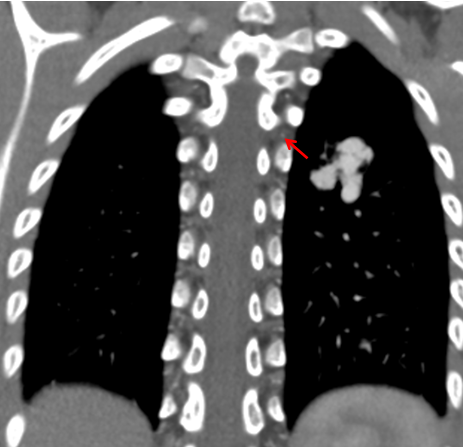

夕夕的異常血管影。

近日,青島婦兒醫(yī)院成功完成一例肺動(dòng)靜脈瘺介入栓塞手術(shù)。6歲的夕夕(化名)在查體時(shí)發(fā)現(xiàn)了肺上長(zhǎng)了一團(tuán)迂曲增粗的異常血管影。雖然孩子除了活動(dòng)耐力略差外,其他方面看起來(lái)一切正常,出于謹(jǐn)慎考慮,夕夕媽媽還是帶著孩子來(lái)到了青島婦兒醫(yī)院。血管瘤&脈管畸形專科醫(yī)師接診后對(duì)孩子進(jìn)行了相關(guān)檢查,診斷夕夕患有“肺動(dòng)靜脈瘺”!